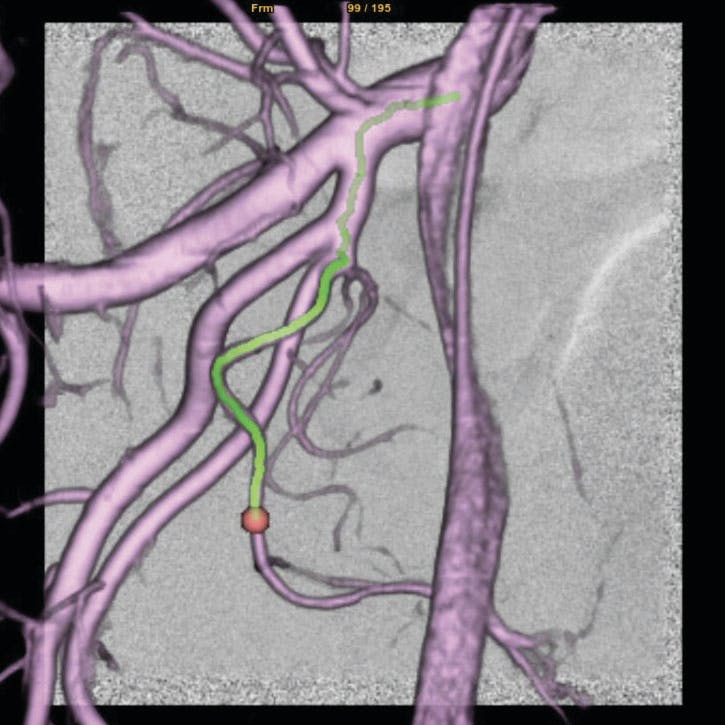

Case Snapshot From Dr. Nutting

A man in his mid 60s presented with BPH and moderate lower urinary tract symptoms. His IPSS (International Prostate Symptom Score) was 18, with a quality of life of 4. The patient noted urinary frequency, urgency, weak stream, and nocturia, with worsening symptoms over the last 5 years. The patient was started on α-blockers, but urinary symptoms recurred after a couple of years. His prostate volume was 108 g. Cystoscopy revealed trilobar hypertrophy and bladder outlet obstruction.

Figure 1. Embo ASSIST (GE HealthCare) navigation software with three-dimensional overlay demonstrating a type 1 prostate artery.

The patient refused transurethral therapies. A bilateral PAE was performed in the OBL. The procedure was technically successful and completed in 56 minutes.